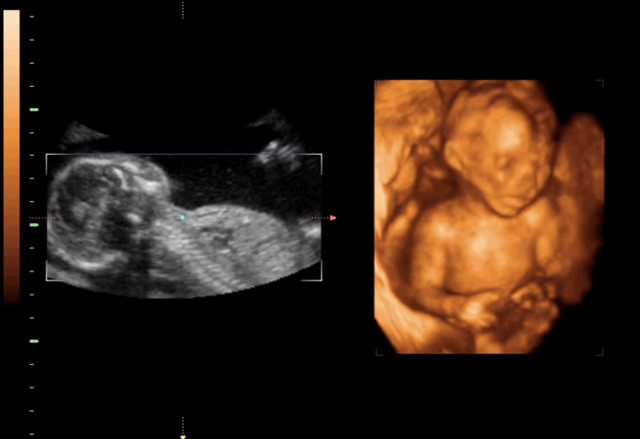

在所有胎儿先天性疾病当中,胎儿唇腭裂,在所有新生儿出生缺陷里排第四位,排在它前面的三位分别是,先天性心脏病、神经系统疾病(如脑积水、脑肿瘤等)、泌尿系统疾病(如肾积水、肾发育不全等)。在所有先天性唇腭裂的胎儿中,大部分是轻度到中度唇裂,有60%-70%不伴随腭裂,有80%仅为单侧唇裂。唇腭裂的胎儿出生后,只是外貌上有些影响,智力、器官发育都没有异常。

30岁的小孙就有唇裂,修补过的疤痕仍很分明。在最近一次三维B超显示,腹中的胎儿居然中度唇裂。她通知大夫,由于她诞生就有唇裂,小时老是被讪笑和厌弃。所有,无论怎样也要流掉腹中的宝宝,她不想让她的孩子再经历这样的经历。